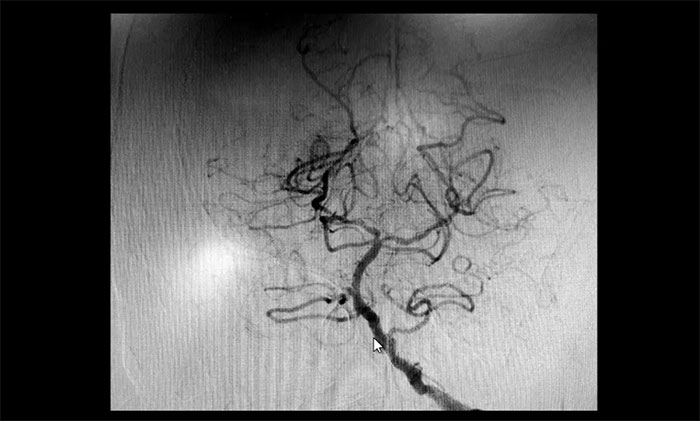

術(shù)后康復(fù)觀察一月余,于耀宇主任團(tuán)隊(duì)再次為曹老伯行右側(cè)頸動(dòng)脈支架置入及左側(cè)椎動(dòng)脈支架置入手術(shù)。術(shù)中造影顯示,右側(cè)頸內(nèi)動(dòng)脈起始段重度狹窄,狹窄長(zhǎng)度8mm左右。左側(cè)椎動(dòng)脈 V4 段重度狹窄,長(zhǎng)度6mm左右。運(yùn)用嫻熟扎實(shí)的技術(shù),在充分做好腦保護(hù)的前提下經(jīng)過(guò)多次球囊擴(kuò)張后,順利釋放支架于狹窄處。造影提示支架打開(kāi)良好,血管狹窄基本恢復(fù)正常,支架貼壁佳,支架內(nèi)血流通暢,遠(yuǎn)端血流良好。

▲ 術(shù)后,右側(cè)頸內(nèi)動(dòng)脈及左側(cè)椎動(dòng)脈狹窄明顯改善